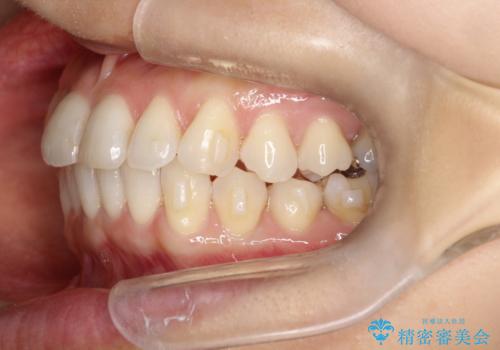

八重歯と前歯のガタガタをインビザラインで

- 八重歯と前歯のガタガタを主訴に来院されました。

目立たず矯正したいとのことでインビザラインで矯正することとしました。

インビザラインで目立たずに治療を終えることができ、喜んでいただけました。